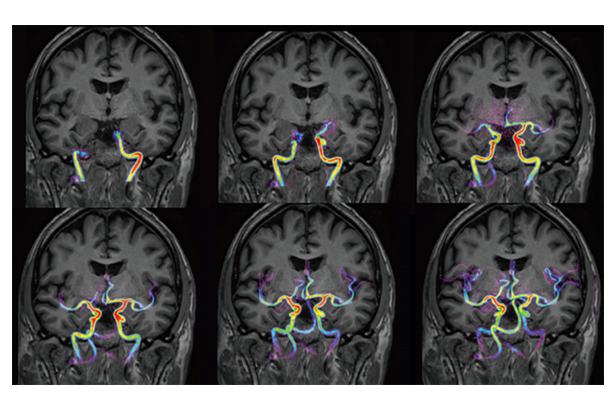

Galan 3T具備高清4D血流成像,類似于DSA,可動態(tài)觀察患者血流信息。高清4D血流成像可避免金屬異物偽影,對于動脈瘤夾閉術、支架等植入物術后血管評估具有臨床價值。